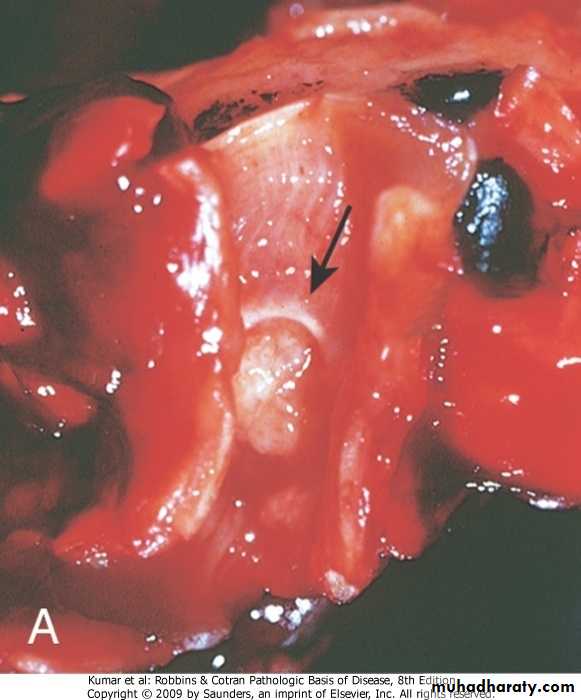

Grossly:

The lung is heavy red congested &edematous

Micro:

Diffuse alveolar wall damage( epithelial & endothelial)

Alveolar wall is lined by hyaline materials Latter on intra alveolar organization takes place